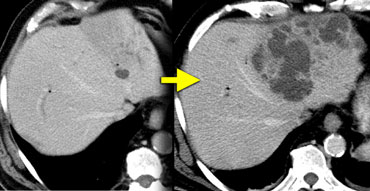

Giant hemangiomas with scar-tissue. Notice that the enhancement matches the bloodpool in all phases. Central scar is hypodens on NECT and stays hypodens. Giant hemangiomas with scar-tissue. Notice that the enhancement matches the bloodpool in all phases. Central scar is hypodens on NECT and stays hypodens.

Large hemangiomas can have an atypical appearance.

Complete fill in is sometimes prevented by central fibrous scarring.

These lesions need to be differentiated from other lesions with a scar like FLC, FNH and Cholangiocarcinoma.

Again looking at the bloodpool will help you.

On the left two large hemangiomas.

Notice that the enhancing parts of the lesion follow the bloodpool in every phase, but centrally there is scar tissue that does not enhance.